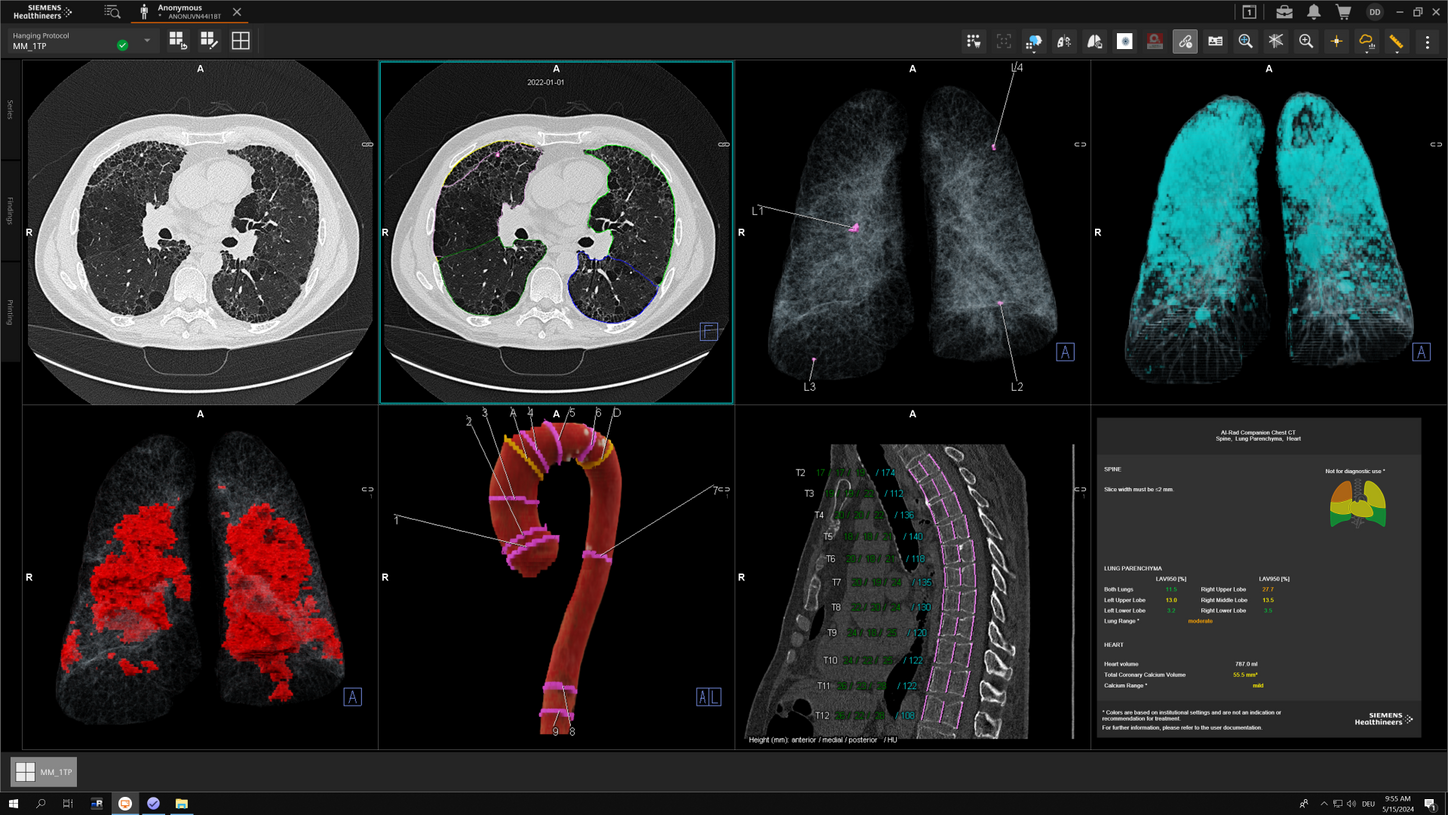

We are empowering decision making for technologists, radiologists, and clinicians along the whole imaging value chain and making it even smarter – allowing healthcare professionals to make the right decision at the right time within the patient pathway. Our AI-powered solutions are not just tools but essential allies in the modern medical imaging landscape, designed to increase productivity, improve clinical precision, and be integrated seamlessly.

Along the imaging pathway there are plenty of levers for productivity and clinical precision

Use seamlessly integrated intelligence to acquire the best images and accelerate your decision making and reporting process through the smart use of data and AI technology. Explore each step within the smart imaging value chain to learn more about our AI portfolio in radiology.

Siemens Healthineers' AI-powered solutions in practice

Discover how Siemens Healthineers' AI-powered solutions are used every day. Watch the video and learn how our technology improves our customers' workflows.